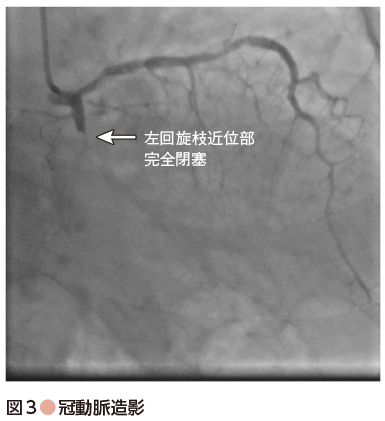

心臓カテーテル検査を施行したところ,左回旋枝領域が近位部で完全閉塞の所見を認めた(図3).よって,今回の胸痛の原因,また心原性ショックの原因は左回旋枝領域の急性心筋梗塞と診断.血圧低下も遷延していたため,昇圧薬サポートを行い,同部位に対してPCIを行った.最終的に完全閉塞部位に対して薬剤溶出性ステントを1本留置し,手技終了.その後,胸痛症状も改善,バイタルサインも改善.血圧は180 mmHg程度まで上昇したため,昇圧薬使用も中止とした.